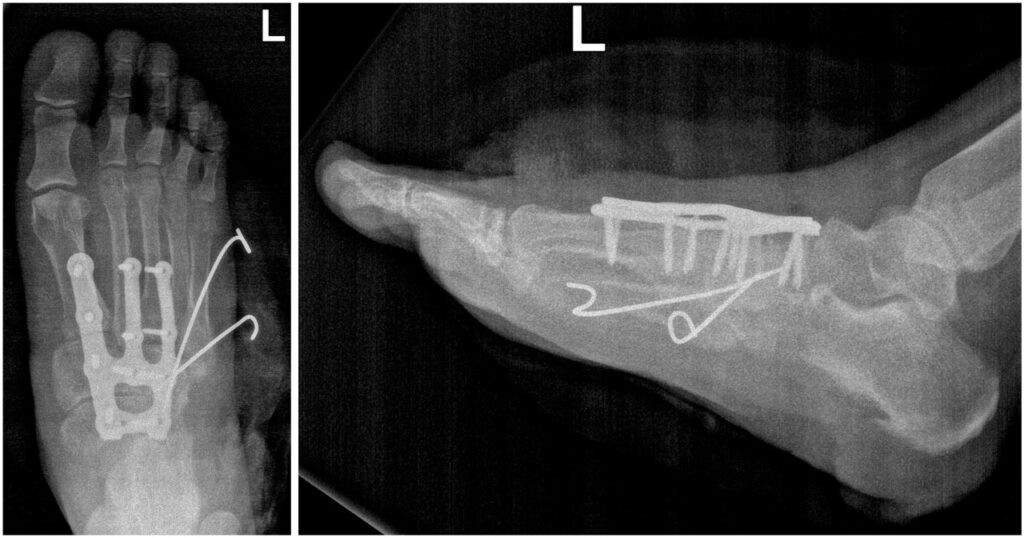

Персонализированный подход к лечению пациентов — важнейший принцип в работе врачей Новосибирского НИИ травматологии и ортопедии. Детальное планирование позволяет учесть все нюансы деформации, снизить риски осложнений, а также добиться большей эффективности операции.